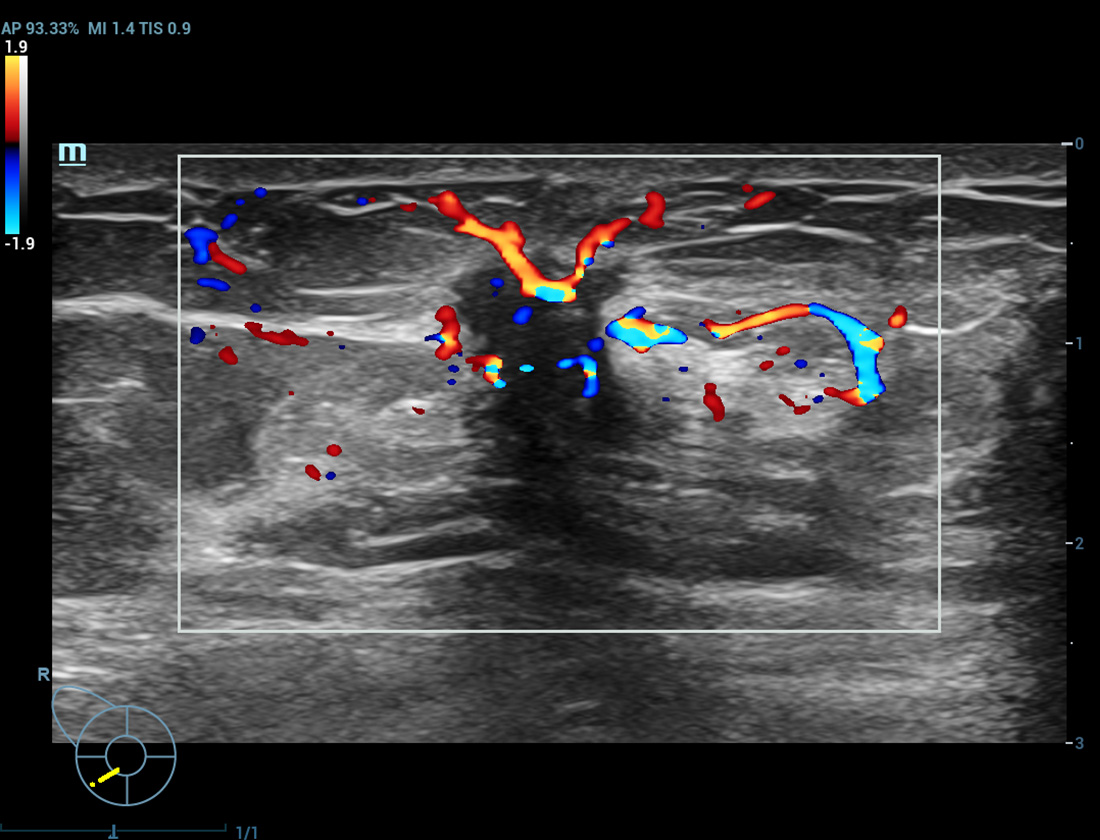

Ultra-micro-angiografie

Breng kleurendoppler op een hoger niveau

Ultra-Micro-angiografie (UMA)

UMA verbetert het diagnostische vertrouwen door de zichtbaarheid van de bloedstromen uit te breiden tot op het kleinste vaatniveau, met een superieure gevoeligheid en resolutie van de bloedstroom.

sUMA Nier

pUMA Borstmassa

sUMA Schildklierkanker